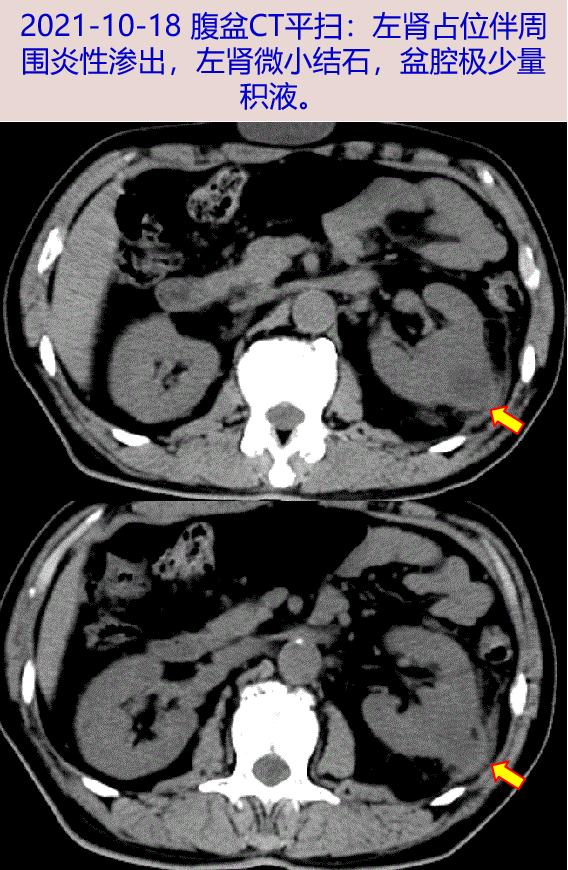

2021-10-18 出现发热、寒战,Tmax 40℃,至我院急诊查血常规WBC 11.09X10^9/L,N 63.6 %,CRP 68.6mg/L,PCT 0.85ng/mL,尿常规:白细胞酯酶++,白细胞镜检 100/HP,蛋白+,隐血-。胸部CT平扫:两肺少许慢性炎症及慢性炎性结节;腹盆CT平扫:左肾占位伴周围炎性渗出,左肾微小结石,盆腔极少量积液。肾脏彩超见左肾中部22×29mm混合回声团块,边界清,周边见数个点状强回声伴彗尾,左肾囊实性占位考虑良性病变可能。予头孢唑肟钠抗感染、赛洛多辛对症处理排尿不畅等治疗。